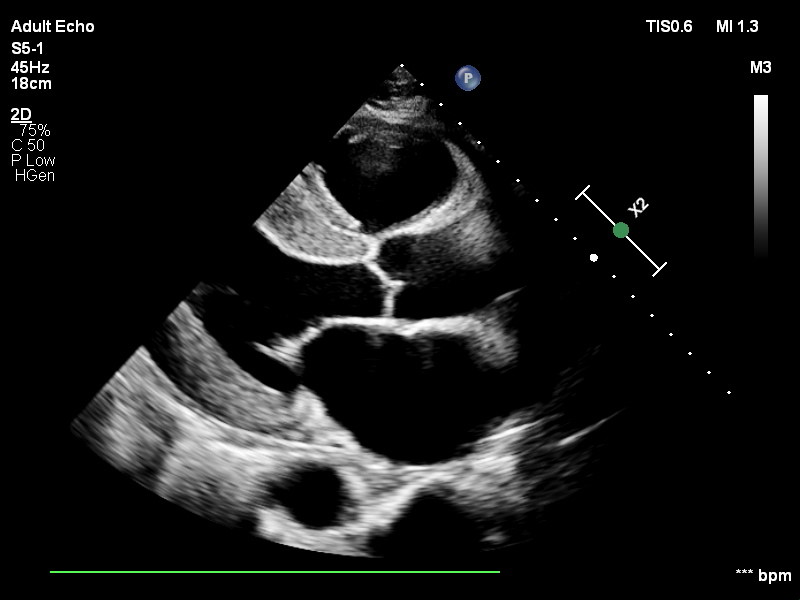

Figure 3 - Echocardiogram showing left ventricular hypertrophy.

Reference - Case courtesy of Karen Machang'a, https://radiopaedia.org/?lang=us - Radiopaedia.org. From the https://radiopaedia.org/cases/187225?lang=us

The heart must work against elevated arterial pressure (increased afterload), leading to compensatory changes:

- Left ventricular hypertrophy (LVH): Concentric hypertrophy to maintain wall stress

- Systolic heart murmur: From dynamic outflow obstruction or concurrent mitral regurgitation

- Gallop rhythm (S4): Indicates reduced ventricular compliance

- Arrhythmias: Ventricular ectopy or atrial fibrillation

- Epistaxis: Nasal vessel rupture from elevated pressure